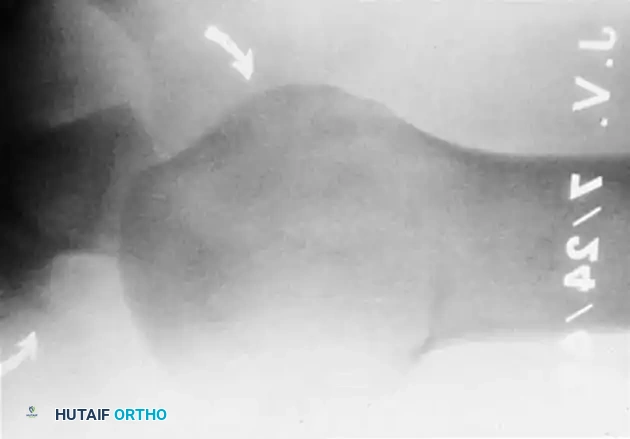

Fig. 54-12 CT scan of humeral head–splitting fracture.